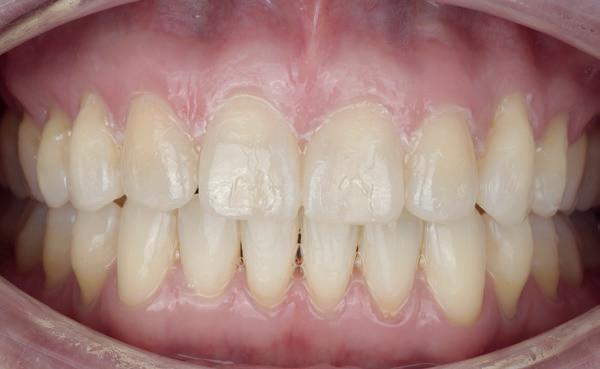

Een 47-jarige vrouw wordt aan het einde van het orthodontische traject door haar eigen tandarts naar mij verwezen voor een intake en eventuele behandeling. Bij mevrouw zijn elementen 12 en 22 afwezig. De 13 en 23 zijn gemesialiseerd. Haar eigen tandarts vraagt of ik het front met composiet kan restaureren om weer een harmonieuze glimlach te krijgen (Afbeelding 1).

Tijdens de intake wordt een complete lichtfoto status gemaakt om de positie van de elementen goed in kaart te brengen en een behandelplan op te kunnen stellen. Op de close-up foto van het bovenfront (afbeelding 2) zien we dat er sprake is van slijtage aan element 11. Elementen 12 en 22 zijn afwezig en elementen 13 en 23 zijn gemesialiseerd. Tussen element 11 en 13 is er sprake van een diasteem. Dit diasteem is niet aanwezig aan de andere zijde (afbeelding 3).

Dit zorgt voor een lastige situatie, omdat bij het sluiten van dit diasteem (dit is de wens van de patiënt) elementen 13 en 11 breder zullen worden dan elementen 21 en 23. Dit is één van de redenen waarom ik patiënten altijd graag aan het einde van het orthodontist traject wil zien. Op dat moment is het nog mogelijk om kleine wijzigingen door te voeren, voordat de beugel definitief wordt verwijderd. Na de intake stuur ik een terugrapportage naar de orthodontist waarbij ik vraag om de elementen zo te positioneren dat de ruimte beter verdeeld is.

Ik zie mevrouw een aantal weken later terug voor evaluatie (afbeelding 4). Er is een klein centraal diasteem ontstaan en daardoor is het diasteem tussen de 11 en 13 ook kleiner geworden. Tussen de 21 en 23 is geen diasteem aanwezig (afbeelding 5), waardoor er hoogstwaarschijnlijk wel iets breedte verschil zal zijn tussen de linker- en rechterzijde.

Met composiet wordt een snelle mock-up gemaakt om te beoordelen of ik in deze situatie goed kan uitkomen met de ruimte, of dat we wellicht de elementen nog meer moeten verplaatsen (afbeelding 6). Mevrouw is zeer tevreden met de snelle mock-up en daarom wordt besloten dat de orthodontische behandeling afgerond kan worden. Eventuele verschillen in breedte kunnen we proberen optisch zoveel mogelijk te maskeren.

Nadat de vaste apparatuur verwijderd is (afbeelding 7 en 8), zie ik mevrouw voor het maken van een afdruk/scan ten behoeve van een wax-up. Aangezien ik in deze casus wil werken met de injectietechniek, is een wax-up noodzakelijk.

1: Glimlach foto om de positie van de elementen ten opzichte van de lippen te beoordelen.

2: Close-up foto van de voortanden in de bovenkaak.

3: Occlusale foto om de positie van de elementen en de diastemen te beoordelen.

4: Situatie na orthodontische aanpassingen.

5: Occlusale foto om de nieuwe positie van de elementen te beoordelen.

6: Snelle mock-up met composiet om te bepalen of de huidige stand van de elementen de ruimte biedt om de elementen in de juiste vorm op te bouwen.

7: Glimlach foto na verwijderen van de vaste apparatuur.

8: Close-up foto van voortanden na verwijderen vaste apparatuur.